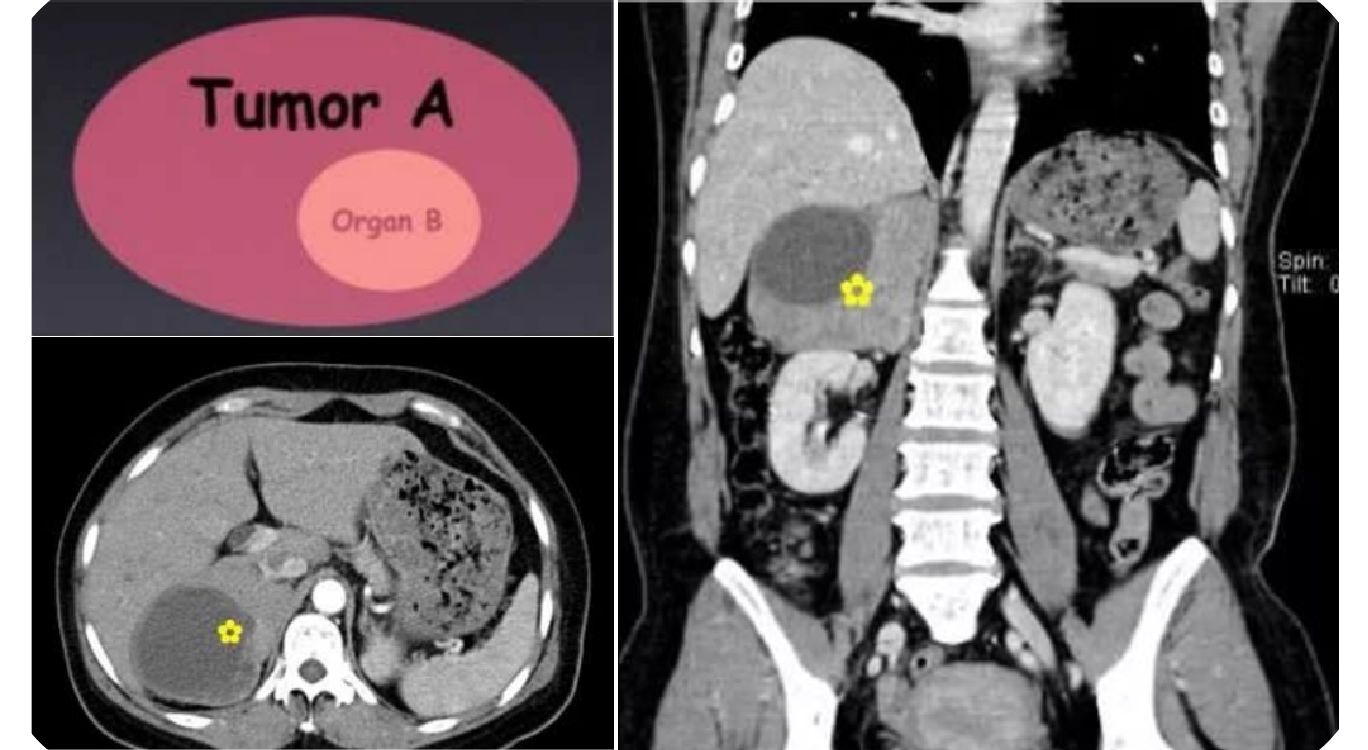

腹膜后平滑肌肉瘤的生长方式主要有三种:① 完全长在血管外,最常见(62%);② 完全长在血管内,最少见(5% );③ 同时长在血管内外 (33%)。

9a0ccceeef94130db73768fa4105b91c.png 图 29:平滑肌肉瘤与血管腔的关系示意图

2f530b96476cae13672532ff0a7ab285.png 图 30:平滑肌肉瘤的三种生长方式(① 血管腔内;② 血管内外;③ 血管腔外)

腹膜后平滑肌肉瘤多位于左上腹膜后、盆底。瘤体多较大,形态不规整呈分叶状改变。常与主动脉及下腔静脉分界不清,容易侵犯腹膜后大血管,此征像较有特征。肿瘤单发多见,多发少见,体积一般较大,有包膜(不同参考资料表述有异),形态一般呈椭圆形或分叶状,密度不均匀,实性部分呈明显低密度,囊变、坏死、出血多见,如肿瘤内有出血,低密度区内可出现高密度影,但肿瘤钙化少见。肿瘤血供多丰富,增强扫描呈轻度渐进性强化或中度至明显强化。肿块常与下腔静脉或其它大静脉分界不清。一般没有淋巴结转移,血行肝转移最多见。

917bfe88330e9a51bacfc381b0a24818.png 病例 6:腹膜后平滑肌肉瘤2例

(① 血管内外;② 血管腔外)① 腹膜后肿块可见侵犯右肾血管、下腔静脉,密度不均匀,有囊变坏死,增强后边缘性延迟环状强化。② 腹膜后肿块与右肾血管,下腔静脉及腹主动脉分界不清,肿块密度不均匀,内可见囊变坏死区及高密度灶(平滑肌肉瘤瘤内如有出血,低密度区内可见高密度出血影,但通常不钙化),增强扫描呈明显不均匀强化,囊变区未见强化。